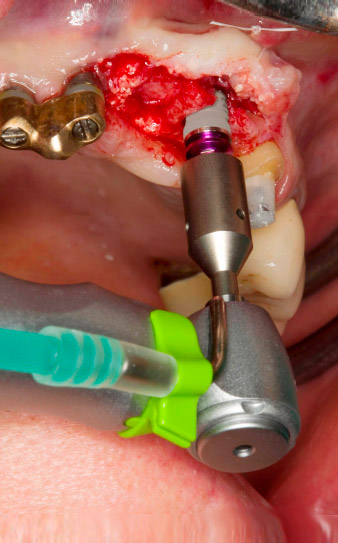

Dopo la prima guarigione, i tessuti molli sono stati sagomati con un ponte rivestito nella porzione basale. Due mesi dopo, il sito è stato esposto con una leggera incisione sula cresta palatoalveolare (Fig. 2). Si è visto che le dimensioni dell'osso alveolare erano sufficienti in corrispondenza della posizione 22. Le figure 2 e 4 mostrano la preparazione della sede di impianto, l'avvitamento e l'impianto utilizzando Implantmed.

Il nuovo motore per implantologia è stato utilizzato con i manipoli chirurgici contrangoli W&H appropriati.

Per compensare la perdita ossea periodontale e ottenere un risultato estetico piacevole, si è proceduto all'impianto unitamente alla rigenerazione guidata dell'osso (tecnica GBR) con materiale di riempimento xenogenico e membrana di collagene (Fig. 5 e 6).